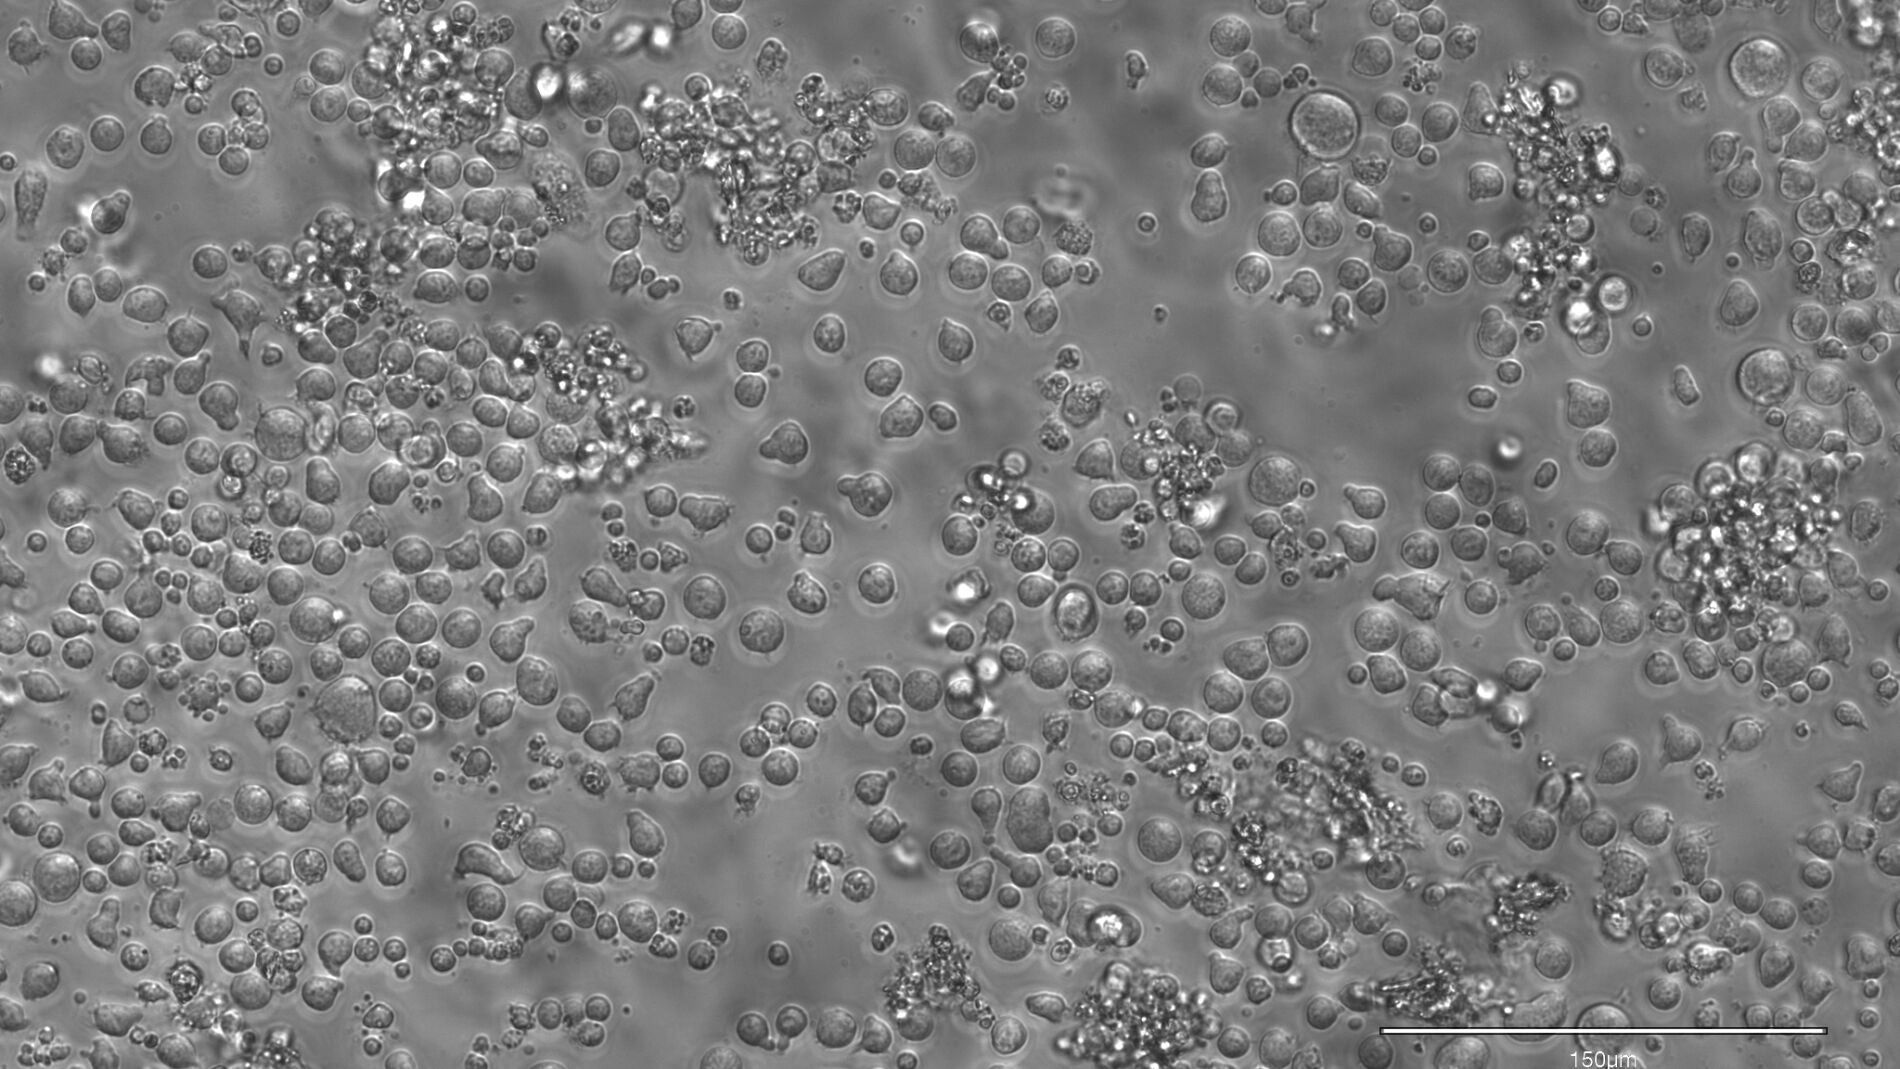

Para ello, los investigadores desarrollaron EPI-Clone, una técnica gracias a la cual es posible leer estos códigos de barras de metilación en cada una de las células y de esta manera pudieron generar mapas que revelan información acerca de qué células madre se expanden y, por lo tanto, contribuyen a la sangre y cuáles se extinguen a lo largo del tiempo.

Gracias a ello, los investigadores pudieron observar que en la sangre de las personas jóvenes hay una gran cantidad de células madres diferentes, las cuales producen un conjunto diverso y variado de células, mientras que a edad avanzada, principalmente a partir de los 50 años, unas pocas se imponen a sus vecinas, tomando gradualmente el control de la producción de sangre. A partir de los 60 años de edad, este fenómeno es aún más evidente y pronunciado.